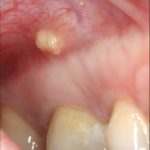

Первое, что чаще всего замечает пациент – небольшой мешочек на мягких тканях во рту, немного напоминающий прыщ. При этом десна отекает, краснеет, а в пораженной области наблюдается пульсирующая боль, свидетельствующая об образовании очага с гноем. Болевые ощущения усиливаются при надавливании на место рядом с образованием. Зубы, рядом с которыми появилась фистула, могут стать более подвижными. Еще один тревожный симптом – неприятный запах изо рта. Несмотря на довольно явные признаки, глядя на них, можно перепутать свищ с другими недугами:

- Киста– небольшой мешочек со скоплением гноя. Ее нужно удалять как можно быстрее, так как образование замещает здоровые ткани, разрушает челюсть и может привести к раку.

- Жировик– появляется при нарушении липидного обмена в клетках. Особой опасности не представляет, но мешает человеку говорить, принимать пищу. Часто жировики появляются у маленьких детей, особенно на стадии прорезывания зубов.

- Прыщ с гноем– это образование резко увеличивается в размерах, требуя срочного вмешательства.